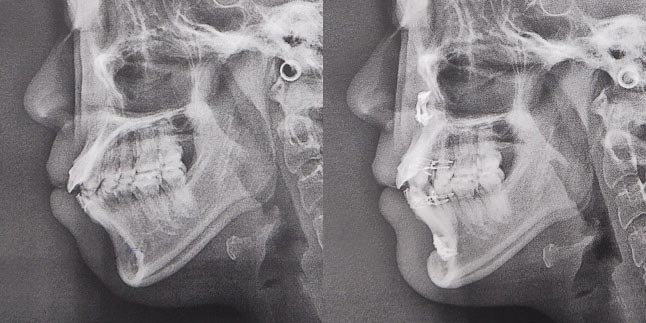

大阪府 19歳 男性

執刀医 辻和志

【治療内容】上下セットバック…上のアゴと下のアゴの両方が前に出ていた為、上下のアゴの骨を切って後ろに下げました。

【費用】上下セットバック 2,307,800円(税込)

【リスク】全身麻酔で行うため全身の健康状態が悪い方は行うことができません。また、手術当日は安静にしていただく必要があります。